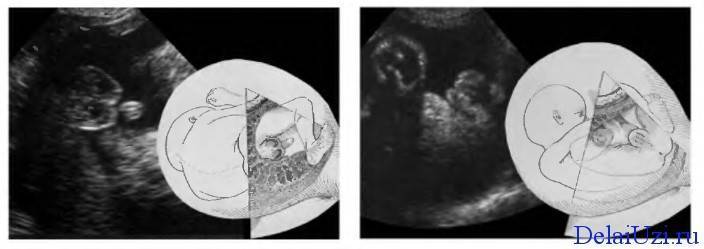

На картинке УЗИ снимок плода мальчика

развитие половых органов по мужскому (1) и женскому (2) типу